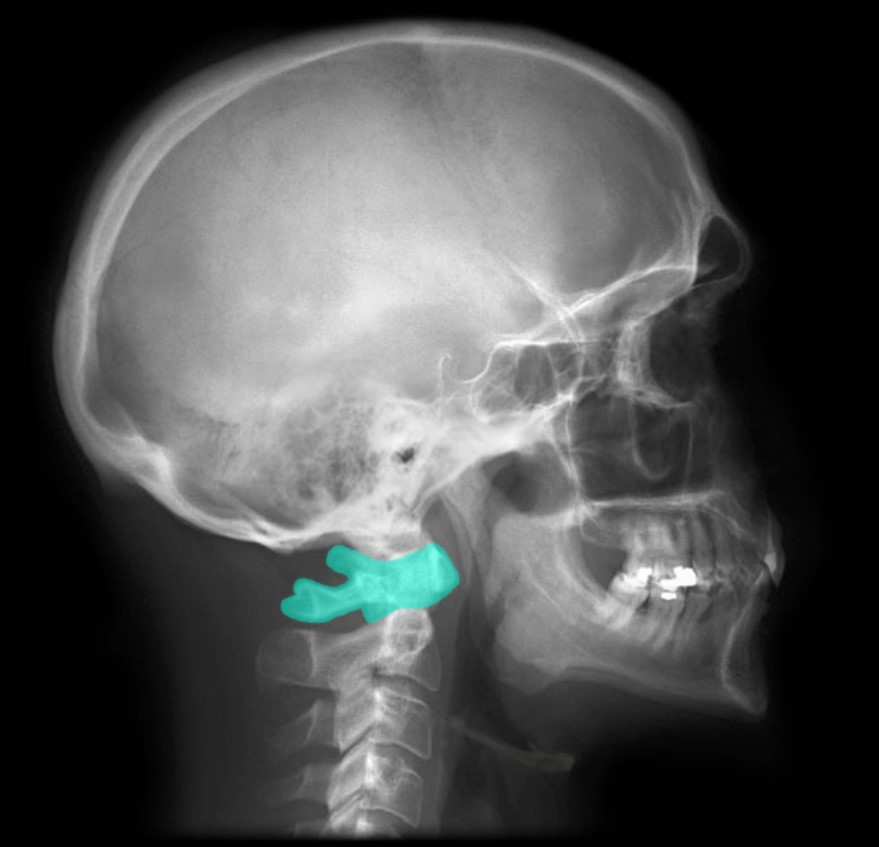

Hyoid